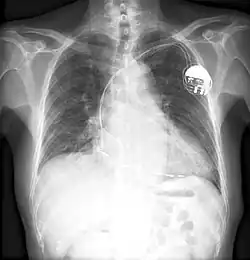

Boykin patented as many as 26 devices.[12] He is best known for inventing multiple different electronic control devices in guided missiles, IBM computers, and in the pacemaker.[13] One of his early inventions was an improved wire resistor, which had reduced inductance and reactance, due to the physical arrangement of the wire.[14]

Other notable inventions include a variable resistor used in guided missiles. His most famous invention was likely a control unit for the artificial cardiac pacemaker.[4] The device essentially uses electrical impulses to maintain a regular heartbeat. Among his other inventions is a burglar-proof cash register.[15]